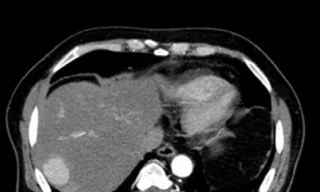

TPO - Bệnh viện Bệnh Nhiệt đới Trung ương thời gian gần đây liên tiếp tiếp nhận các ca suy gan nặng, trong đó nhiều bệnh nhân có tiền sử viêm gan B mạn tính nhưng không theo dõi và điều trị thường xuyên. Tình trạng chung ở những trường hợp này là sự chủ quan, thiếu hiểu biết và thói quen tự ý dùng thuốc trong thời gian dài.

TPO - Viêm gan B là một bệnh truyền nhiễm do virus viêm gan B (HBV) gây ra, có thể dẫn đến các biến chứng nghiêm trọng như xơ gan, suy gan và ung thư gan. Điều nguy hiểm của căn bệnh này là bất cứ ai cũng có khả năng mắc bệnh, hơn nữa, khả năng lây lan của virus viêm gan B lại “rất nhanh, rất nguy hiểm”.

TP - Tại Việt Nam, tỉ lệ nhiễm viêm gan B ước tính 8-10% dân số, nghĩa là có 8 đến 10 triệu người mắc bệnh. Thống kê của ngành Y tế cho thấy, có đến 90% số ca ung thư gan là ung thư biểu mô tế bào gan. Đây là vấn đề đáng lo ngại với số tử vong cao khoảng 25.000 trường hợp/năm.